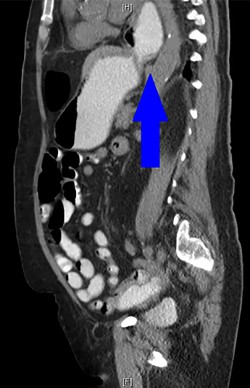

During the hospitalization, initial cardiac workup with 12-lead electrocardiogram and serial troponins was negative. The patient’s oncologic medications were held without improvement of the pain as well as to prevent leukopenia and neutropenia, if surgery was indicated. Palliative care was unable to achieve adequate pain control with oral and IV medications, and the patient did not want to pursue hospice care. Surgical consultation was obtained, and further evaluation with a CT scan of the chest, abdomen and pelvis with oral and IV contrast demonstrated an anteromedial diaphragmatic defect through which a prominent amount of mesenteric fat and a portion of the colon herniated representing a Morgagni hernia (Figs. 1–4). An increase in the size of the previously known PEH as well as the Morgagni hernia was noted. Due to continued chest pain unrelieved by opioids, a joint decision was made between surgeon, oncologist and the patient to proceed with surgery. She underwent successful robotic laparoscopic repair of the Morgagni hernia and PEH with dulex mesh for reinforcement. Her chest pain subsequently resolved. The patient gradually tolerated oral feeds and was eventually discharged in stable condition.

A sagittal view from the 2017 CT chest, abdomen and pelvis with IV and PO contrast demonstrates the Morgagni hernia with fat sweeping up through the diaphragmatic defect (red arrow) and a retrocardiac paraesophageal hernia (blue arrow).

A CT abdomen and pelvis with oral contrast from 2015 demonstrates the presence of a PEH, identified by the blue arrow.